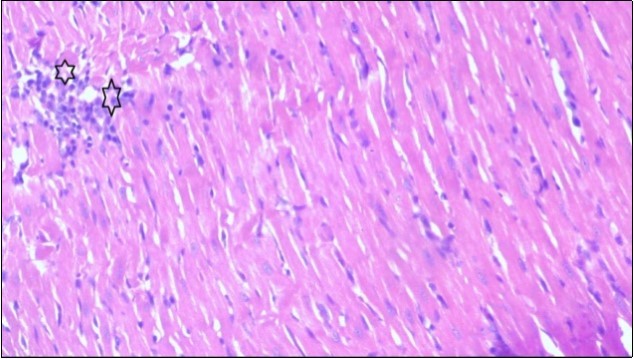

An important organ that is affected directly by the obesity which is the heart: The heart is the main important organ in circulatory system, the heart wall has three basic layers; the tunica intima of the heart is called endocardium, the tunica media of the heart is called the myocardium, the tunica adventitia of the heart the epicardium. The histological examination of the hearts of control rats feeding standard diet showing normal cardiac tissue with elongated, unbranched multinucleated muscle fibers (arrow), (Figure 1). The rats are feeding (HFD) for 2 weeks (obese rats) showing large number of inflammatory cells (star), degeneration muscles fiber ,circle and congested Blood vessels (arrow) (Figure 2). By comparison hearts of rats are treated by fennel after obesity and control rats observed show improved cardiac tissue with less infiltration (star) and well organized elongated muscle fibers with peripheral nuclei (arrow) (Figure 3). While examination of rats heart that treated by ator after obesity appears show less improved cardiac tissue with few inflammatory cells between disorganized muscle fiber (star), (Figure 4). While combined hearts of rats are treated by fennel and ator after obesity and control mice are showing nearly cardiac tissue with well-organized muscles fibers (arrow), (Figure 5).

Figure 4.Photomicrograph of heart section of treated rat with Ator drug showing less improved cardiac tissue with few inflammatory cells between disorganized muscle fiber (star), (H&E) (400X).

These results were confirmed with histological changes of feeding rats heart tissues with high fat diet only, which showed vaculation of tunica media and narrowing in the lumen of aorta sections as well as congestion of cardiac blood vessel and hyalinosis of its wall. This result was confirmed by Szilvassy et al., 78, who indicated that although hyperlipidemia increases oxidative stress in the cardiovascular system, it renders the heart and the vasculature more susceptible to stress. Ouwens et al. 79 identified that development of hyper-cholestremia, which is one of the risk factors for cardio vascular diseases is associated with increased blood levels of TC, LDL-C and VLDL-C as well as lowered levels of HDL in rats fed on high fat-diet. This result was confirmed by histological study, which revealed apparent normal histological structure of heart in all treated rats with fennel seeds. Epidemiologic studies have shown an inverse correlation between HDL-C level and the risk of cardiovascular disease. Increasing the HDL cholesterol level by 1mg may reduce the risk of cardiovascular disease by 2 to 3 percent 80. The present data agreed with Fatiha et al. 81, who reported that hyper-lipidemic rats treated with fennel extract had significant decrease in plasma levels of TL, TG, TC, LDL-C and VLDL, and significant increase in HDL-C level. The current study demonstrates that the alteration induced by high fat diet causing changes in blood parameters. These changes are exhibited through a decrease in RBCs, Ht, Hb and platelet and these changes could be due to oxidative stress, which lead to lipid peroxidation in RBCs membranes, auto oxidation of hemoglobin. As regards the total WBCs, lymphocytes and monocytes showed a marked decrease. While a distinct increase in the percentage of neutrophils and esinophils. The present, demonstrates that rats treated with (fennel), (ator) and (fennel with ator) exposure provided significant protection to the altered haematological variables. The effect of the treatment with fennel and ator is more effective than fennel only or ator only. The current study showed that the serum levels of the total protein and albumin in the obese group were significantly higher than those of the control group. The administration of (fennel) revealed significant decrease in the serum levels of the albumin and total protein as compared to the obesity group, although the serum levels of the albumin and total protein of the Ator group less than the obesity group. Otherwise, the levels of the total protein and albumin in fennel and Ator group were near to the similar value of the control group. The finding of this study indicates that the concentration of Malondialdehyde (MDA) and Myeloperoxidase (MPO) in liver homogenates of the fennel and ator group significant decrease than group (3) and group (4) and obesity group. There is a growing awareness that obesity is a prime risk factor for the development of dyslipidemia profile and that oxidative stress may play a role in various adverse effects of obesity.